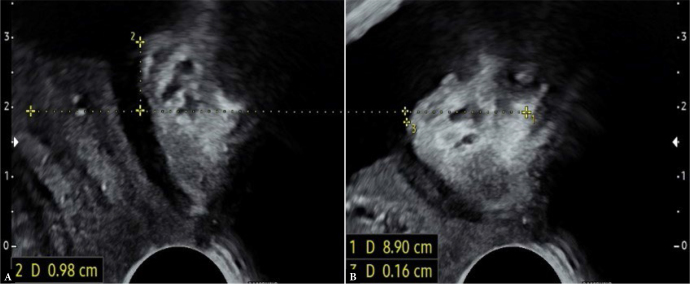

目的:本研究旨在探讨尿动力学检查中观察到的特定尿道功能参数与盆底超声评估的部分尿道特征之间的相关性。此外,我们还对因压力性尿失禁而接受外科治疗的女性患者进行了评估。材料与方法:对192例女性患者行无耻骨后张力阴道胶带手术治疗应激性尿失禁进行回顾性研究。在静息剖面术中评估最大尿道闭合压力和功能尿道长度。超声测量,连同漏斗的评估,作为盆底检查的一部分,按照Kociszewski描述的技术进行。有临床意义的盆腔器官脱垂、前房室手术史、既往放疗或膀胱过度活动症状的患者被排除在分析之外。结果:对尿动力学和超声检查结果进行统计学评价。所分析的尿动力学和超声参数之间没有相关性。在所有被评估为适合放置无张力阴道胶带的压力性尿失禁患者中,证实了长尿道漏斗。结论:结果表明尿动力学检查和超声检查评估尿道解剖和功能的不同方面,因此它们的结果不能互换使用。所有临床和尿动力学证实的压力性尿失禁患者在盆底超声检查中均发现长尿道漏斗。

Aim: This study aimed to examine the correlations between specific urethral function parameters observed in urodynamic testing and selected urethral characteristics evaluated by pelvic floor ultrasonography. Additionally, the presence of urethral funneling during straining was evaluated in female patients referred for surgical treatment of stress urinary incontinence.

Material and methods: A retrospective study was conducted on 192 female patients referred for surgical treatment of stress urinary incontinence with the use of retropubic tension-free vaginal tape. Maximum urethral closure pressure and functional urethral length were evaluated urodynamically during resting profilometry. Ultrasound measurements, along with the assessment of funneling, were performed as part of the pelvic floor examination, following the technique described by Kociszewski. Patients with clinically significant pelvic organ prolapse, a history of anterior compartment surgery, prior radiotherapy, or symptoms of overactive bladder were excluded from the analysis.

Results: The values obtained from urodynamic and ultrasound examinations were evaluated statistically. No correlation was identified between the analyzed urodynamic and ultrasound parameters. Long urethral funneling was confirmed in all patients with stress urinary incontinence assessed as eligible for the placement of tension-free vaginal tape.

Conclusions: The results indicate that urodynamic and ultrasound examinations assess distinct aspects of urethral anatomy and function, and therefore their findings cannot be used interchangeably. Long urethral funneling assessed during pelvic floor ultrasonography was noted in all patients with clinically and urodynamically confirmed stress urinary incontinence.